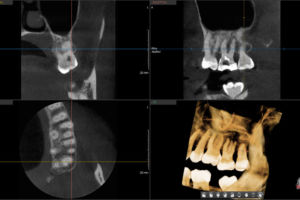

A kollégával történt telefonos egyeztetés után az első konzultációs alkalommal ct készült a páciens fogáról:

Megbeszéltük a mikroszkópos kezelés lépéseit, várható költségeit, a felmerült kérdéseket. A páciens írásos kezelési tervet kapott, ehhez csatolva a kezelés részletes leírását, a lehetséges kockázatokat, utópanaszokat és az egyes kezelések utáni tennivalókat.

Második alkalommal feltártam a pulpakamrát. A palatinális és mb1 csatornák kezelése nem okozott nehézséget. Db-ben a csúcsi görbület hosszasabb megmunkálási időt vett igénybe (milyen jó, hogy csak egy 10-es file járt előttem a gyökércsatornában és nem preparáltak lépcsőt egy 40-sel!). Mb2 egyáltalán nem látszott. Csak a ct alapján tudtam, hogy keresnem kell és a ct alapján tudtam kimérni, hogy pontosan hol.